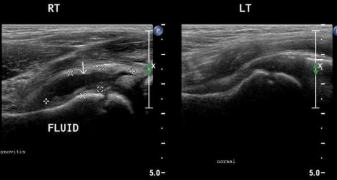

초음파: 고관절 내 액체 증가(염증 소견) 확인

좌: 화살표 검은음영으로 보이는 액체증가소견 우: 반대편 정상모습